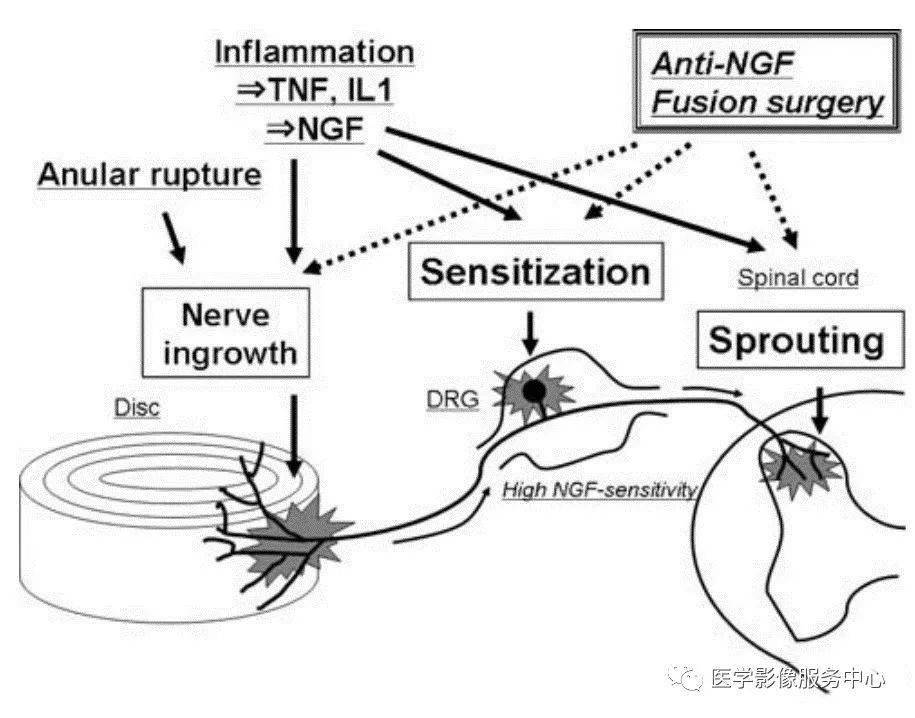

发病机制

椎间盘纤维环外层撕裂后发生的神经末梢及机械感受器伴随血管肉芽组织内长入纤维环内层,甚至髓核。自由的神经末梢在炎症及机械压力作用下会导致周围神经末梢敏化(周围敏化)从而激活疼痛感受器导致腰痛。

图示:椎间盘源性腰痛的发病机制

(Takahashi K. Eur Spine J (2008) 17 (Suppl 4):S428–S431)